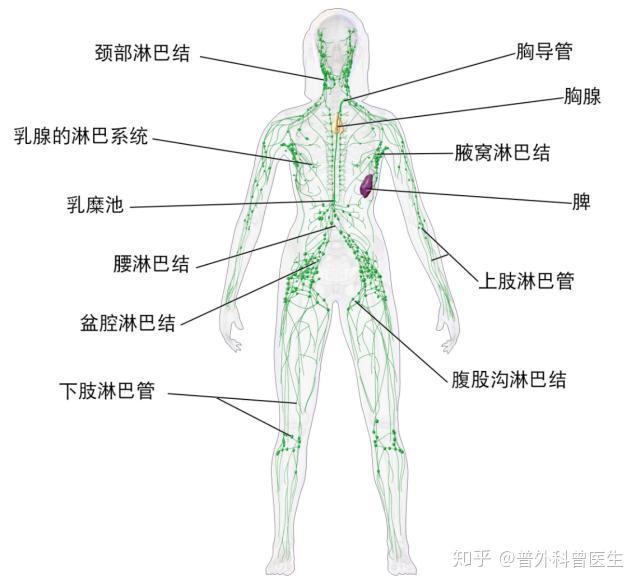

淋巴引流综合消肿疗法(CDT)技术 – 知乎